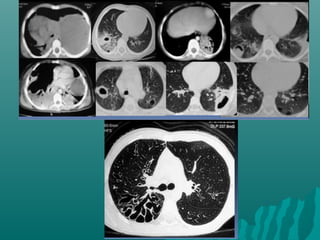

Ventana en TCARVentana en TCAR

 «El grosor de la pared bronquial en TCAR deberá«El grosor de la pared bronquial en TCAR deberá

estudiarse, con un nivel de ventana entre -250 yestudiarse, con un nivel de ventana entre -250 y

-700 UH y una amplitud de ventana mayor de-700 UH y una amplitud de ventana mayor de

1,000 UH.1,000 UH.

 Con una amplitud de ventana inferior a 1,000 UHCon una amplitud de ventana inferior a 1,000 UH

se producirá un engrosamiento artificial de lase producirá un engrosamiento artificial de la

pared bronquial.pared bronquial.

Ortega M y col. Utilidad de la radiografía de tórax yOrtega M y col. Utilidad de la radiografía de tórax y

de la tomografía computada de alta resolución»de la tomografía computada de alta resolución»

Alergia , asma e inmunologia pediatricaAlergia , asma e inmunologia pediatrica

Vol20,num3 sep-dic 2011Vol20,num3 sep-dic 2011